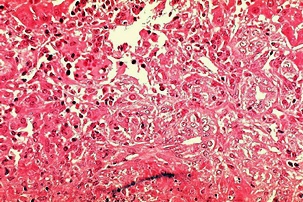

황달이 생기는 이유는 담즙색소라고 알려진 빌리루빈이 과도하게 생기기 때문입니다. 빌리루빈은 우리 몸의 오래된 적혈구가 파괴되면서 생기는 물질인데요. 이 물질은 담즙에 녹아서 우리 몸의 배설물과 함께 배출이 되는 것이 정상적이지만 빌리루빈의 과잉생산이나, 간의 장애, 간세포나 담도의 손상에 의해 빌리루빈이 역류할 경우 발생된다고 합니다.

황달이 생겼을 때 나타나는 대표적인 증상은 소변의 색깔이 진하게 변하는 것입니다. 이는 과도하게 분비된 빌리루빈이 소변으로 배출되기 때문인데요. 이러한 경우 소변의 색이 진한 갈색으로 변하게 됩니다. 또한 피부에 담즙색소가 침착되면 눈이 노랗게 변하는데요. 눈에 노랗게 된다고 모두 황달 증상을 의심할 수 있는 것은 아닙니다.

보통 눈과 피부, 소변의 색깔에 모두 이상이 생긴 경우 황달 증상으로 볼 수 있으며 병원에 내원하여 진단을 받아보는 것이 권장됩니다. 황달이 생기는 경우 피부 가려움증을 동반한다고 하는데요. 이러한 이유는 배출되어야 할 화학물질이 피부의 신경조직을 자극하여 발생한다고 추측하고 있습니다.